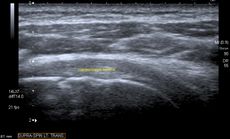

الموجات فوق الصوتية

التصوير بالرنين المغناطيسي